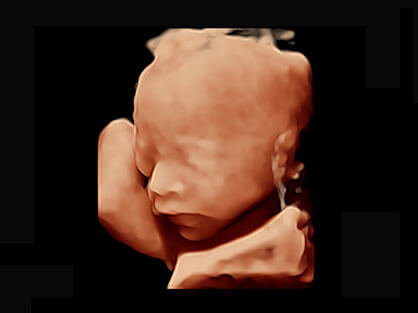

可同时显示组织结构表面和内部的轮廓信息,达到透视效果,为临床提供更丰富的诊断信息。